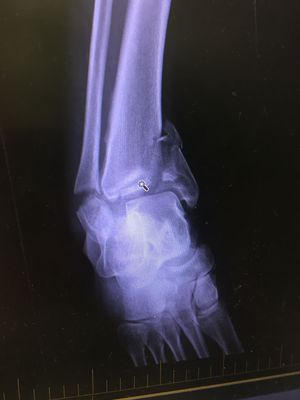

Tib/Fib Vs. Motorbike

Approx 40yr old male, self presented to emergency department post fall off his motor bike. Obvious deformity of his R)ankle. Closed fracture, pt was only in pain on movement.

Tip/fib vs motorbike...motorbike won😞